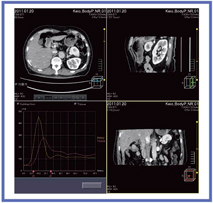

治療前後のCT perfusionを見ると,治療前には比較的vascularityが高い転移巣が見られたが,治療後は明らかに血流の低下が認められる(図2)。解析は,流入血管と対象組織にROIをとり,現在はMaximum Slope法でTBF(組織血流量)を測定する(図3)。今後,Compartment Model法が使えるようになれば,blood volume(BV)やmean transit time(MTT)の計測も可能となると思われる。

![]() 図3 CT perfusionの解析画面 |